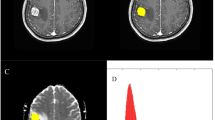

This study aims to investigate the predictive value of preoperative whole-tumor histogram analysis of multi-parametric MRI for histological subtypes in patients with lung cancer brain metastases (BMs) and explore the correlation between histogram parameters and Ki-67 proliferation index. The preoperative MRI data of 95 lung cancer BM lesions obtained from 73 patients (42 men and 31 women) were retrospectively analyzed. Multi-parametric MRI histogram was used to distinguish small-cell lung cancer (SCLC) from non-small cell lung cancer (NSCLC), and adenocarcinoma (AC) from squamous cell carcinoma (SCC), respectively. The T1-weighted contrast-enhanced (T1C) and apparent diffusion coefficient (ADC) histogram parameters of the volumes of interest (VOIs) in all BMs lesions were extracted using FireVoxel software. The following histogram parameters were obtained: maximum, minimum, mean, standard deviation (SD), variance, coefficient of variation (CV), skewness, kurtosis, entropy, and 1st–99th percentiles. Then investigated their relationship with the Ki-67 proliferation index. The skewness-T1C, kurtosis-T1C, minimum-ADC, mean-ADC, CV-ADC and 1st – 90th ADC percentiles were significantly different between the SCLC and NSCLC groups (all p < 0.05). When the 10th-ADC percentile was 668, the sensitivity, specificity, and accuracy (90.80%, 76.70% and 86.32%, respectively) for distinguishing SCLC from NSCLC reached their maximum values, with an AUC of 0.895 (0.824 – 0.966). Mean-T1C, CV-T1C, skewness-T1C, 1st – 50th T1C percentiles, maximum-ADC, SD-ADC, variance-ADC and 75th – 99th ADC percentiles were significantly different between the AC and SCC groups (all p < 0.05). When the CV-T1C percentiles was 3.13, the sensitivity, specificity and accuracy (75.00%, 75.60% and 75.38%, respectively) for distinguishing AC and SCC reached their maximum values, with an AUC of 0.829 (0.728–0.929). The 5th-ADC and 10th-ADC percentiles were strongly correlated with the Ki-67 proliferation index in BMs. Multi-parametric MRI histogram parameters can be used to identify the histological subtypes of lung cancer BMs and predict the Ki-67 proliferation index.